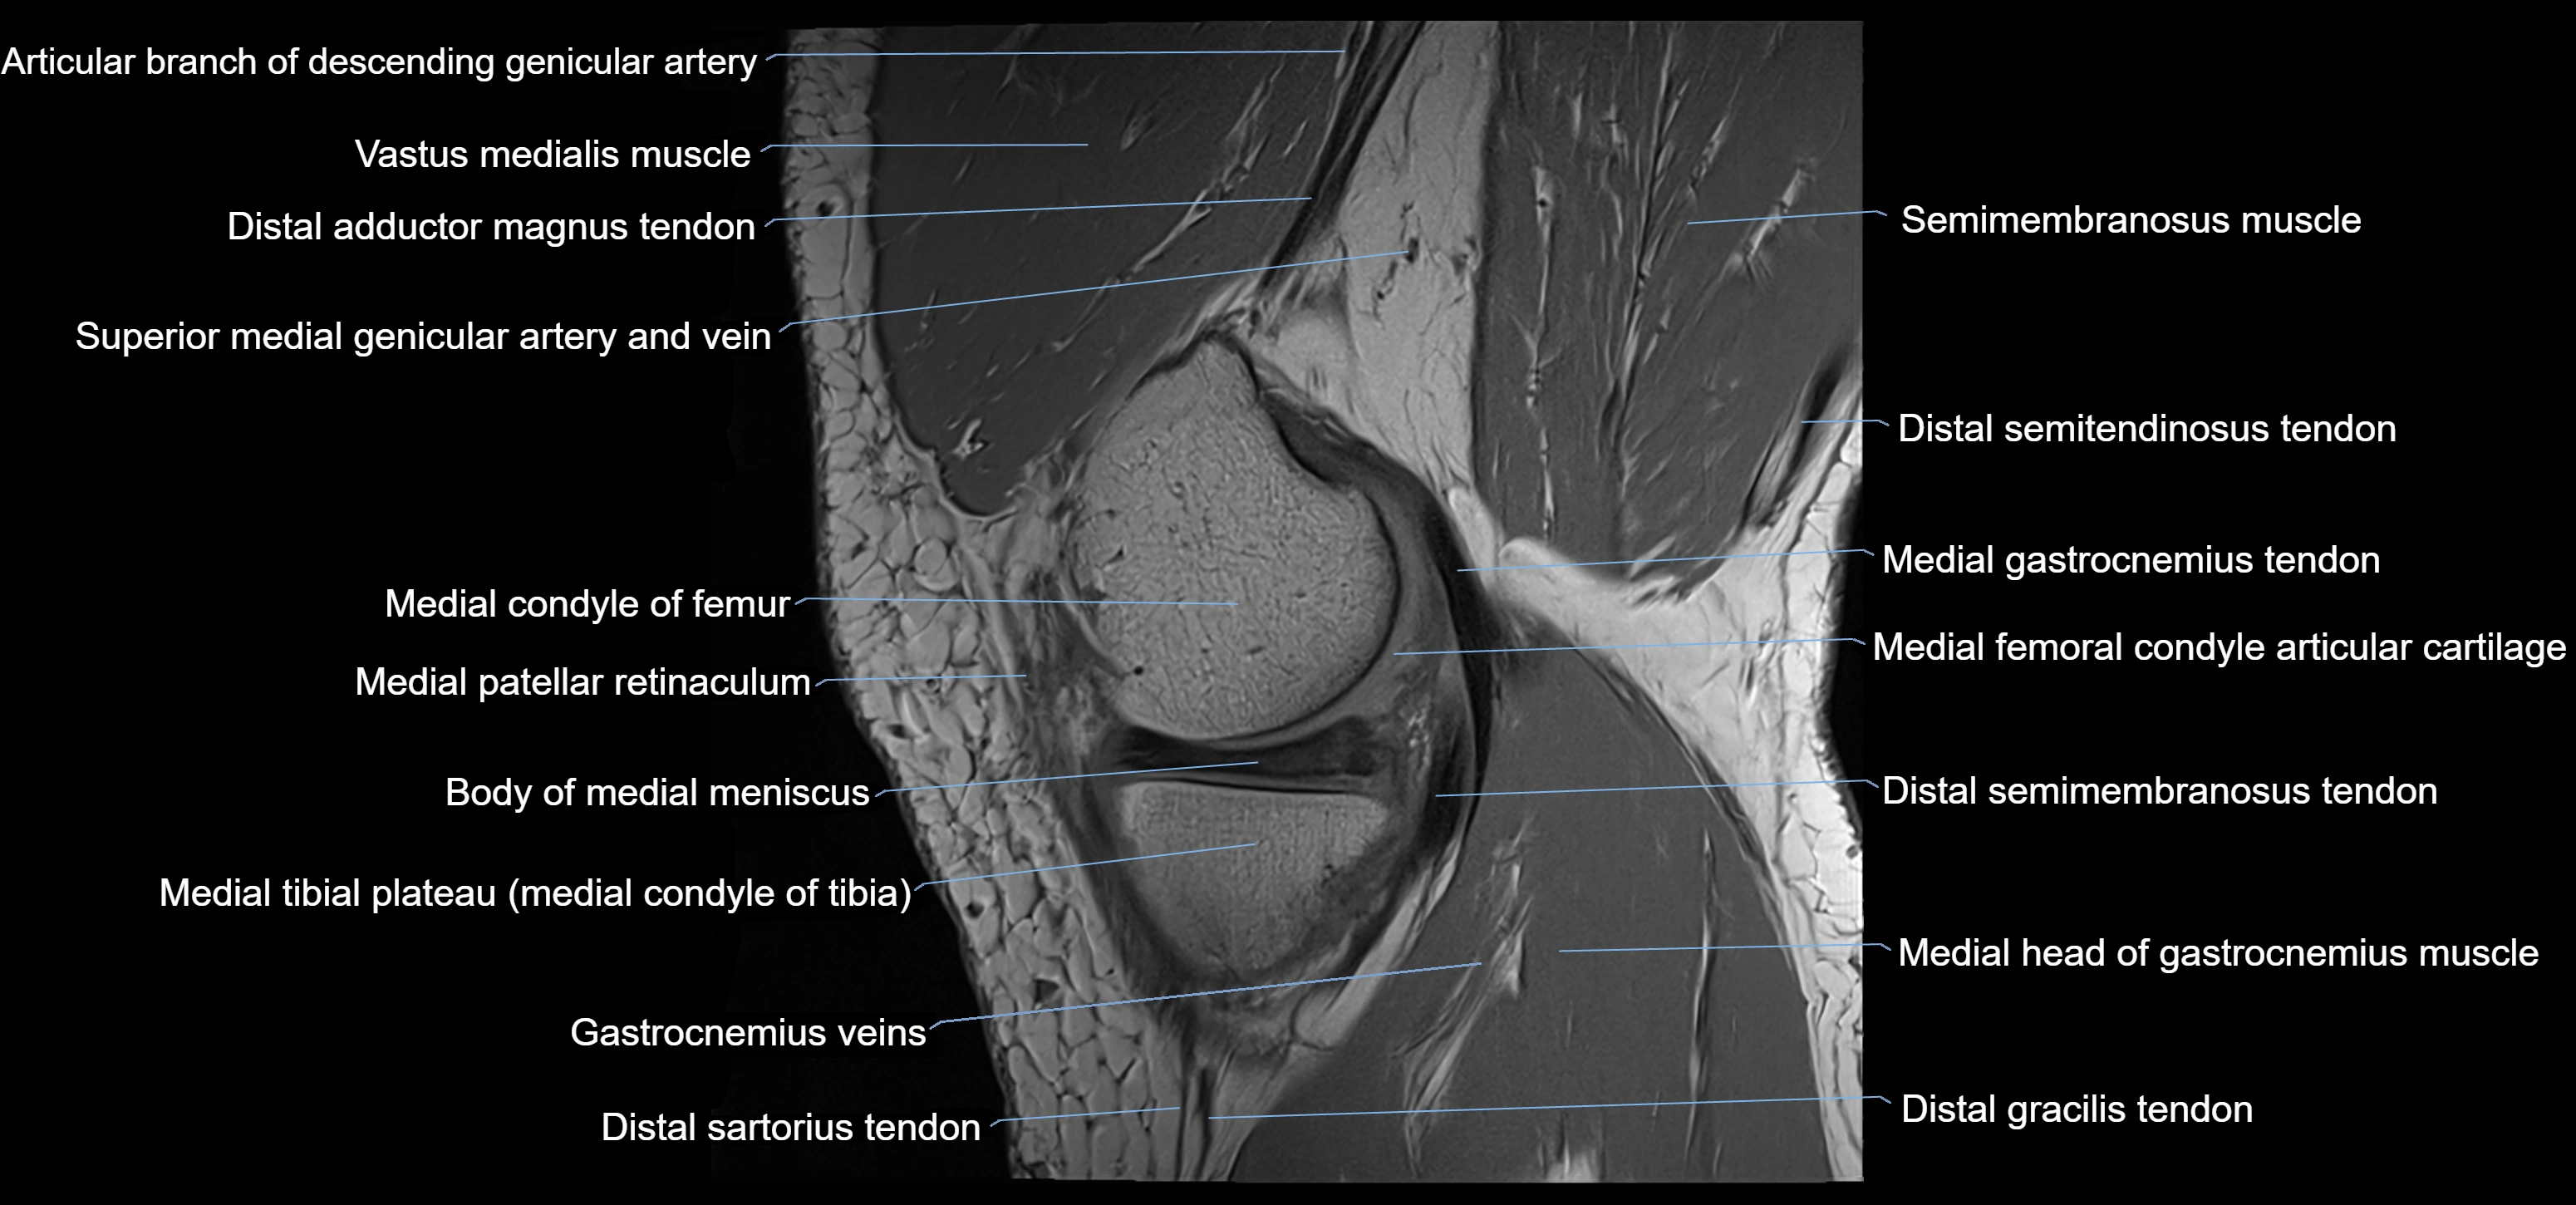

- Body of medial meniscus

- Distal adductor magnus tendon

- Distal semimembranosus tendon

- Distal semitendinosus tendon

- Gracilis tendon (Distal)

- Medial condyle of femur

- Medial condyle of tibia

- Medial gastrocnemius tendon

- Medial head of gastrocnemius muscle

- Medial patellar retinaculum

- Medial tibial plateau

- Semimembranosus muscle

- Superior medial genicular artery

- Vastus medialis muscle